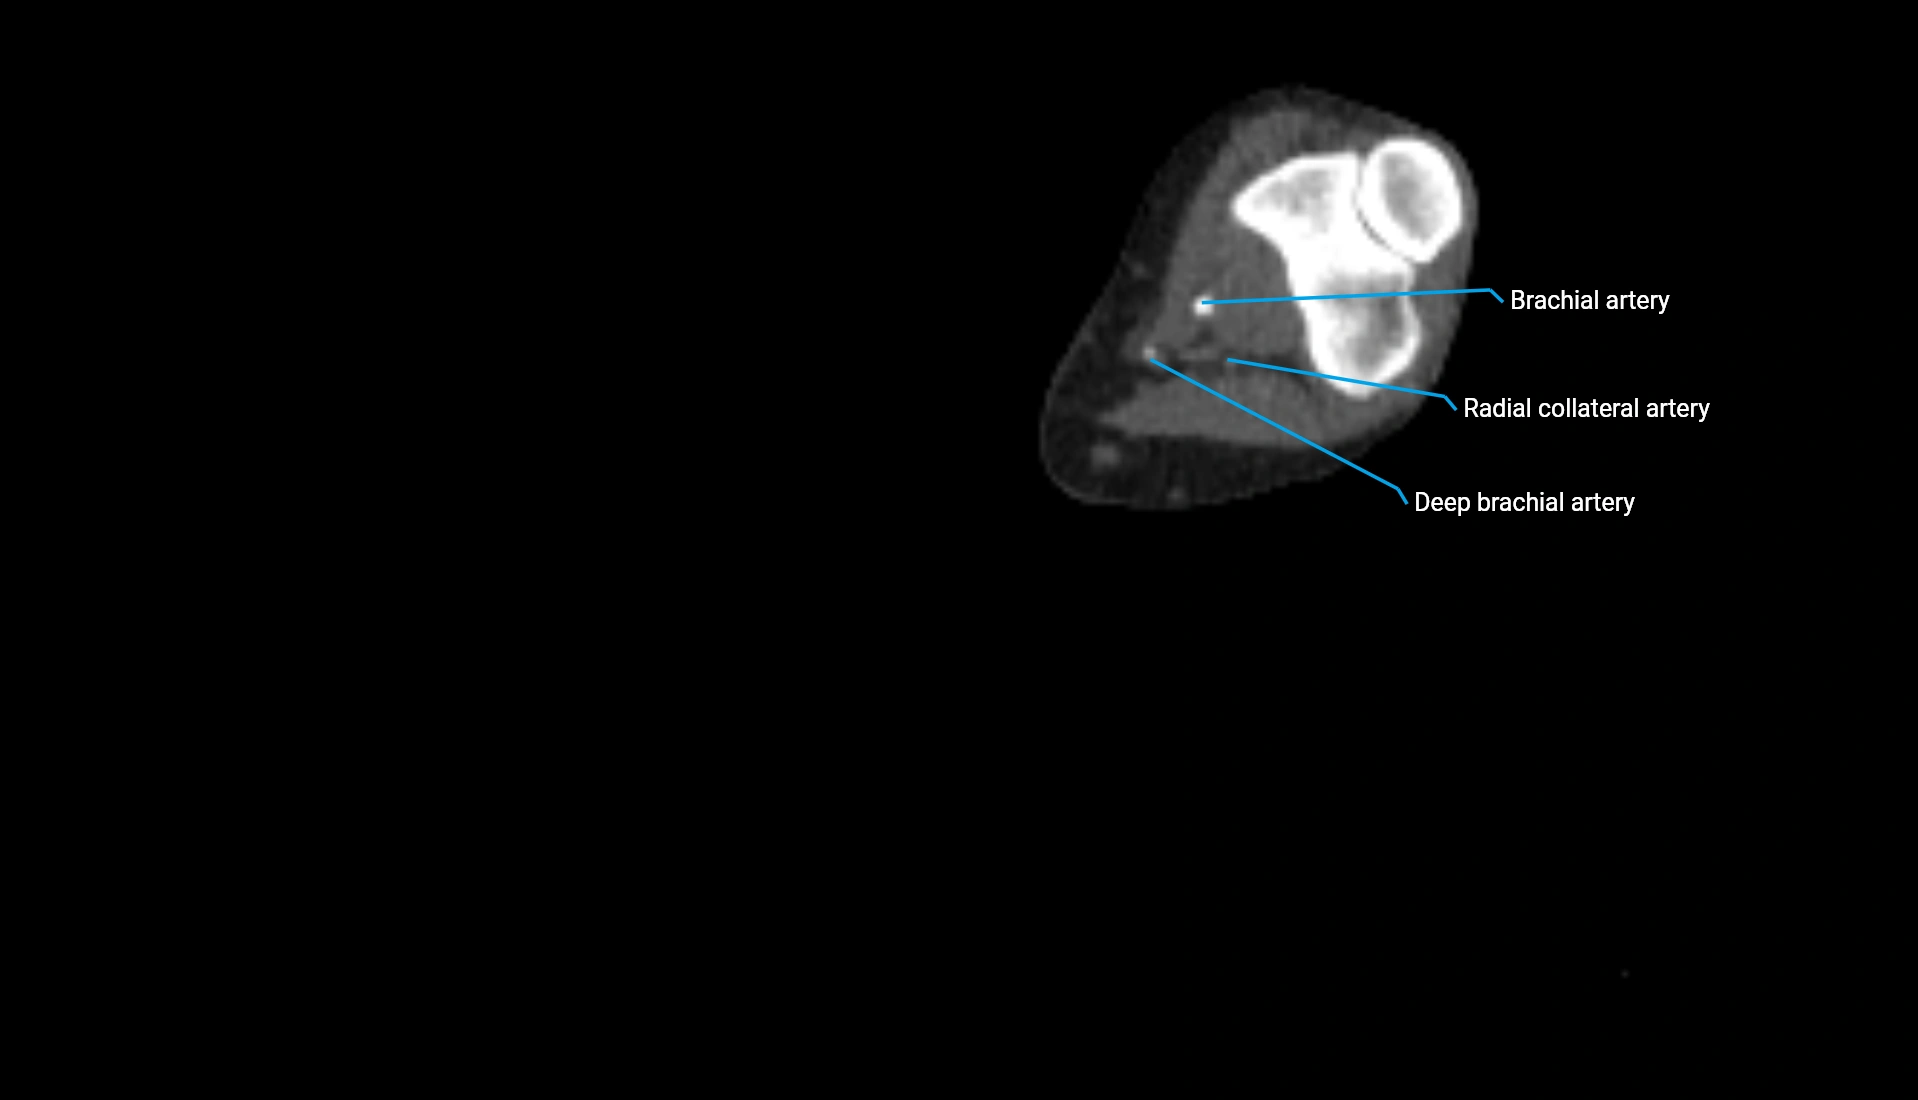

CT Appearance

Non-Contrast CT:

• Cortex: High-density, sharply defined

• Subchondral bone: Dense cancellous matrix

• Articular surface: Smooth concave contour articulating with the capitellum

• Excellent for evaluating bone integrity, alignment, and subtle fractures